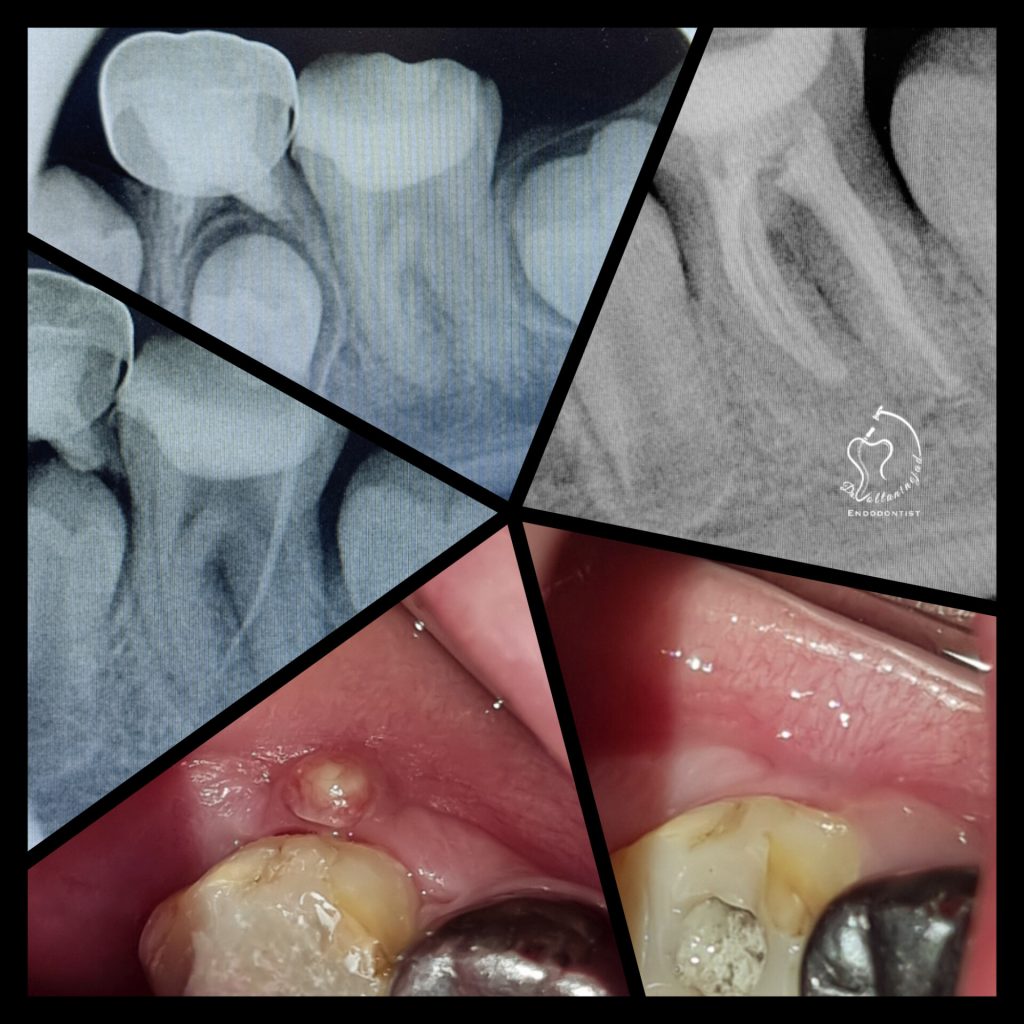

🔹 درمان ریشه دندان با آناتومی نادر

• شرح کوتاه: بیمار ارجاعی با دندان دارای آنومالی (Gemination / دندان دوتایی) که درمان ریشه تخصصی میکروسکوپی با موفقیت انجام شد.

• نتیجه: رفع درد و حفظ دندان به مدت طولانی.

درمان ریشه دندان نادر